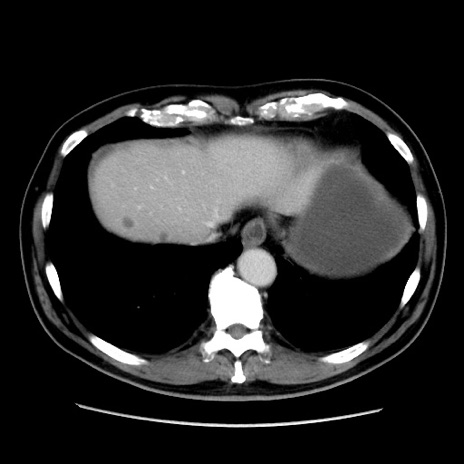

症例16(横断像)

【症例】 70歳代男性

【主訴】 腹痛、嘔吐

【現病歴】 約1ヶ月前より間欠的に腹痛と嘔吐あり、当院消化器内科を受診したところCTで多発する肝臓のLDAを指摘され、精査中であった。以降は消化器症状は安定していたが、2日前より嘔気と腹痛があり、同日より排便・排ガスが消失した。改善認めず、 本日、救急外来を受診した。

【既往歴】 大腸ポリープ切除後。

【身体所見】意識清明・会話良好、BT 36.3℃、BP 127/80mmHg、 P 80bpm、腹部:膨満あり、平坦・軟、上腹部正中および下腹部正中に圧痛あり、反跳痛なし、筋性防御なし。

【データ】WBC 7200、CRP 0.77